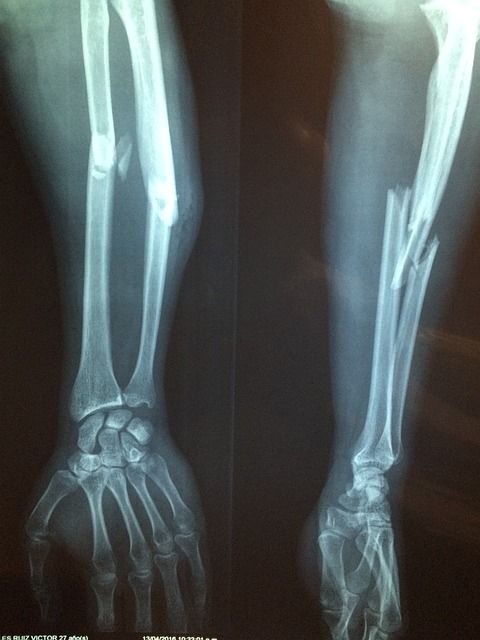

그 외에도 혈액 검사로 요산 농도를 측정하고, X선이나 초음파, CT 등의 영상 검사로 관절 손상과 통풍 결절을 확인할 수 있습니다. 급성 발작 시 혈중 요산 농도가 일시적으로 떨어질 수 있으니, 증상이 없을 때 검사를 반복하는 경우도 있습니다.